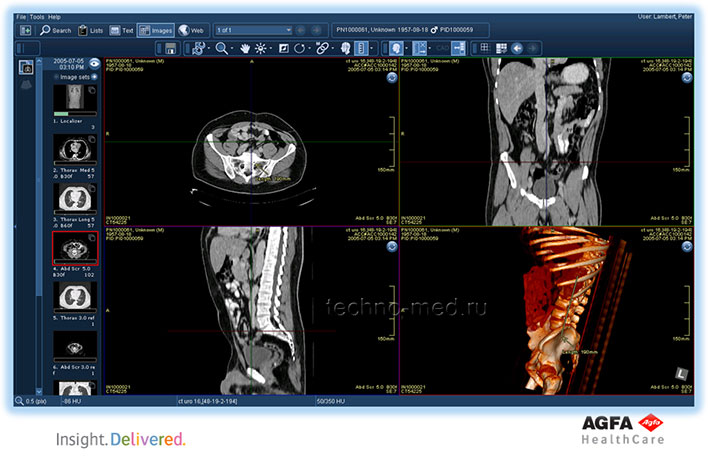

Полный цифровой рабочий процесс для отделения визуализационной диагностики

Рабочий стол технолога